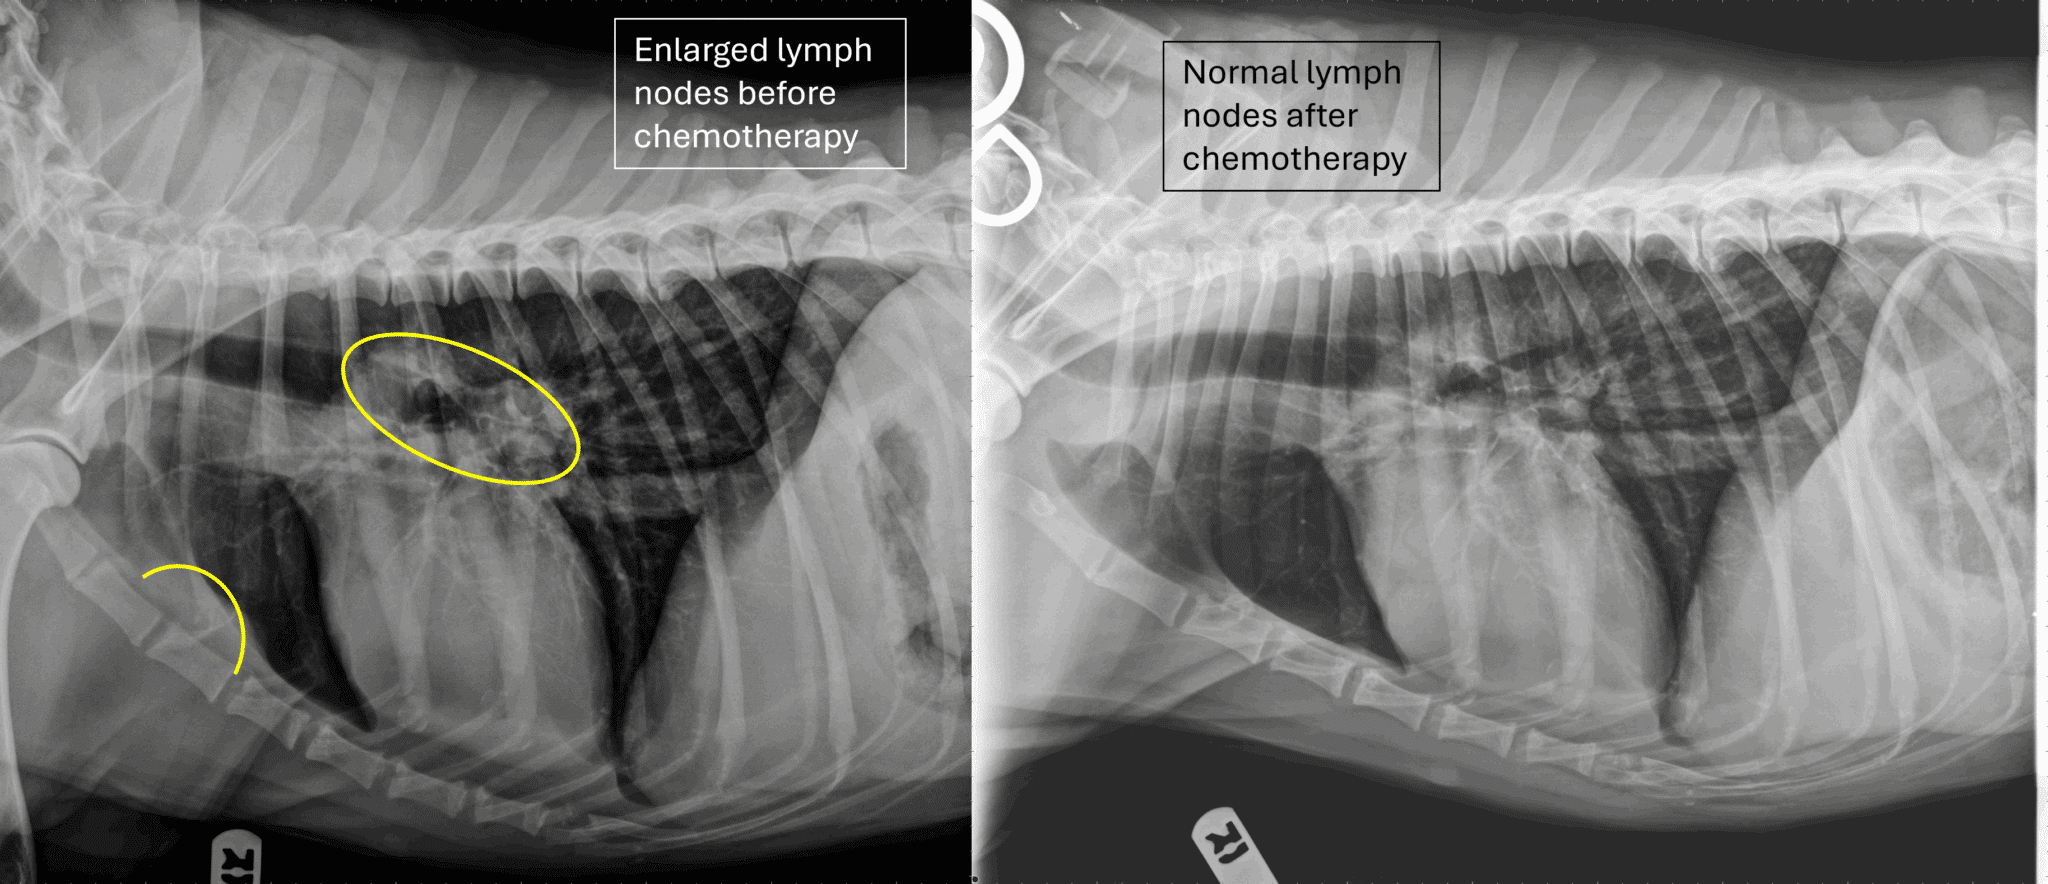

Dogs also have lymph nodes inside their bodies. Veterinarians use x-ray or ultrasound to identify abnormal growth in these nodes.